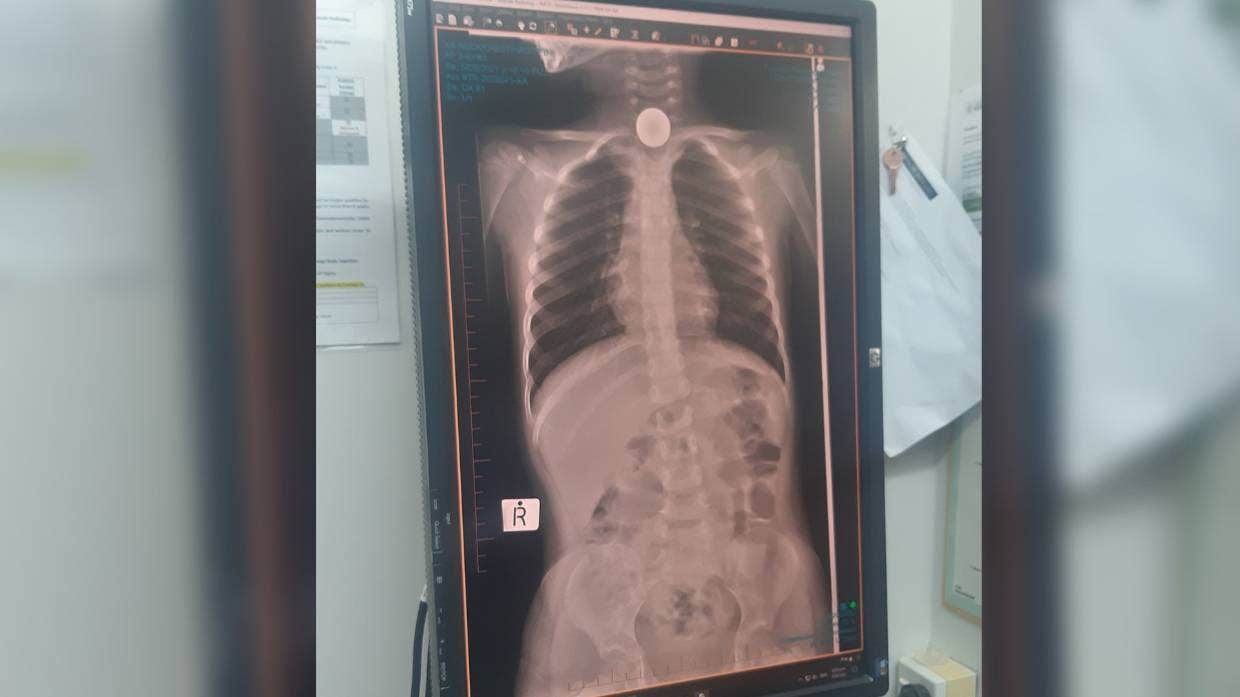

Το νόμισμα -που ήταν και το πρώτο χαρτζιλίκι που έλαβε η μικρή - είχε «καθίσει» σε πολύ άσχημο σημείο, όπως έδειξε η ακτινογραφία, θέτοντας σε κίνδυνο τη ζωή της μικρούλας.

«Μας είπαν ότι είχε σφηνώσει το λάθος σημείο και είχε αρχίζει να πρήζεται πολύ» είπε η μητέρα της ενώ πρόσθεσε «Δεν είχε παραπονεθεί καθόλου ότι κάτι την ενοχλούσε. Ένιωσα απαίσια μαμά».

Ωστόσο, πέρασαν 4 μέρες και το νόμισμα παρέμενε καλά σφηνωμένο στον λαιμό του παιδιού! Την πήγαν στο νοσοκομείο, όπου χρειάστηκε χειρουργείο για να αφαιρέσουν το νόμισμα. Ευτυχώς, το παιδάκι είναι καλά τώρα.